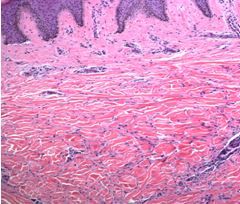

Key Point: The patient presents with a solitary hard brown papule on the trunk. Patient history, morphology, and location favor a diagnosis of dermatofibroma. These lesions may present as papules or nodules which may be elevated or slightly depressed and are typically located over the lower extremities, above the elbows or on the lateral trunk. A dimple sign or depression (Figure 2) is created over a dermatofibroma when it is grasped between thumb and forefinger. Dermatofibromas are more comonly seen in adults and range from 4- to 20-mm in size, although giant lesions, greater than 5 cm in diameter, may occur. Suspected etiology includes skin injury such as insect bites or shaving. Pathology demonstrates a dermal mass composed of fibrous tissue with numerous spindle cells which are factor XIIIA positive (Figure 3).